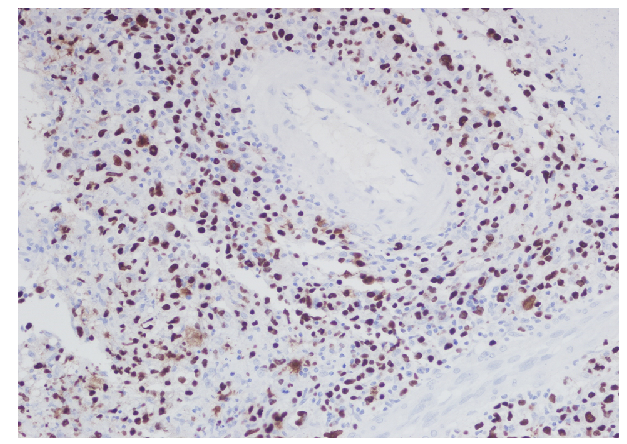

Figure 2 Immunohistochemical stain of the same lymph node showing numerous Ebstein Barr Virus Encoded RNA (EBER) positive cells.